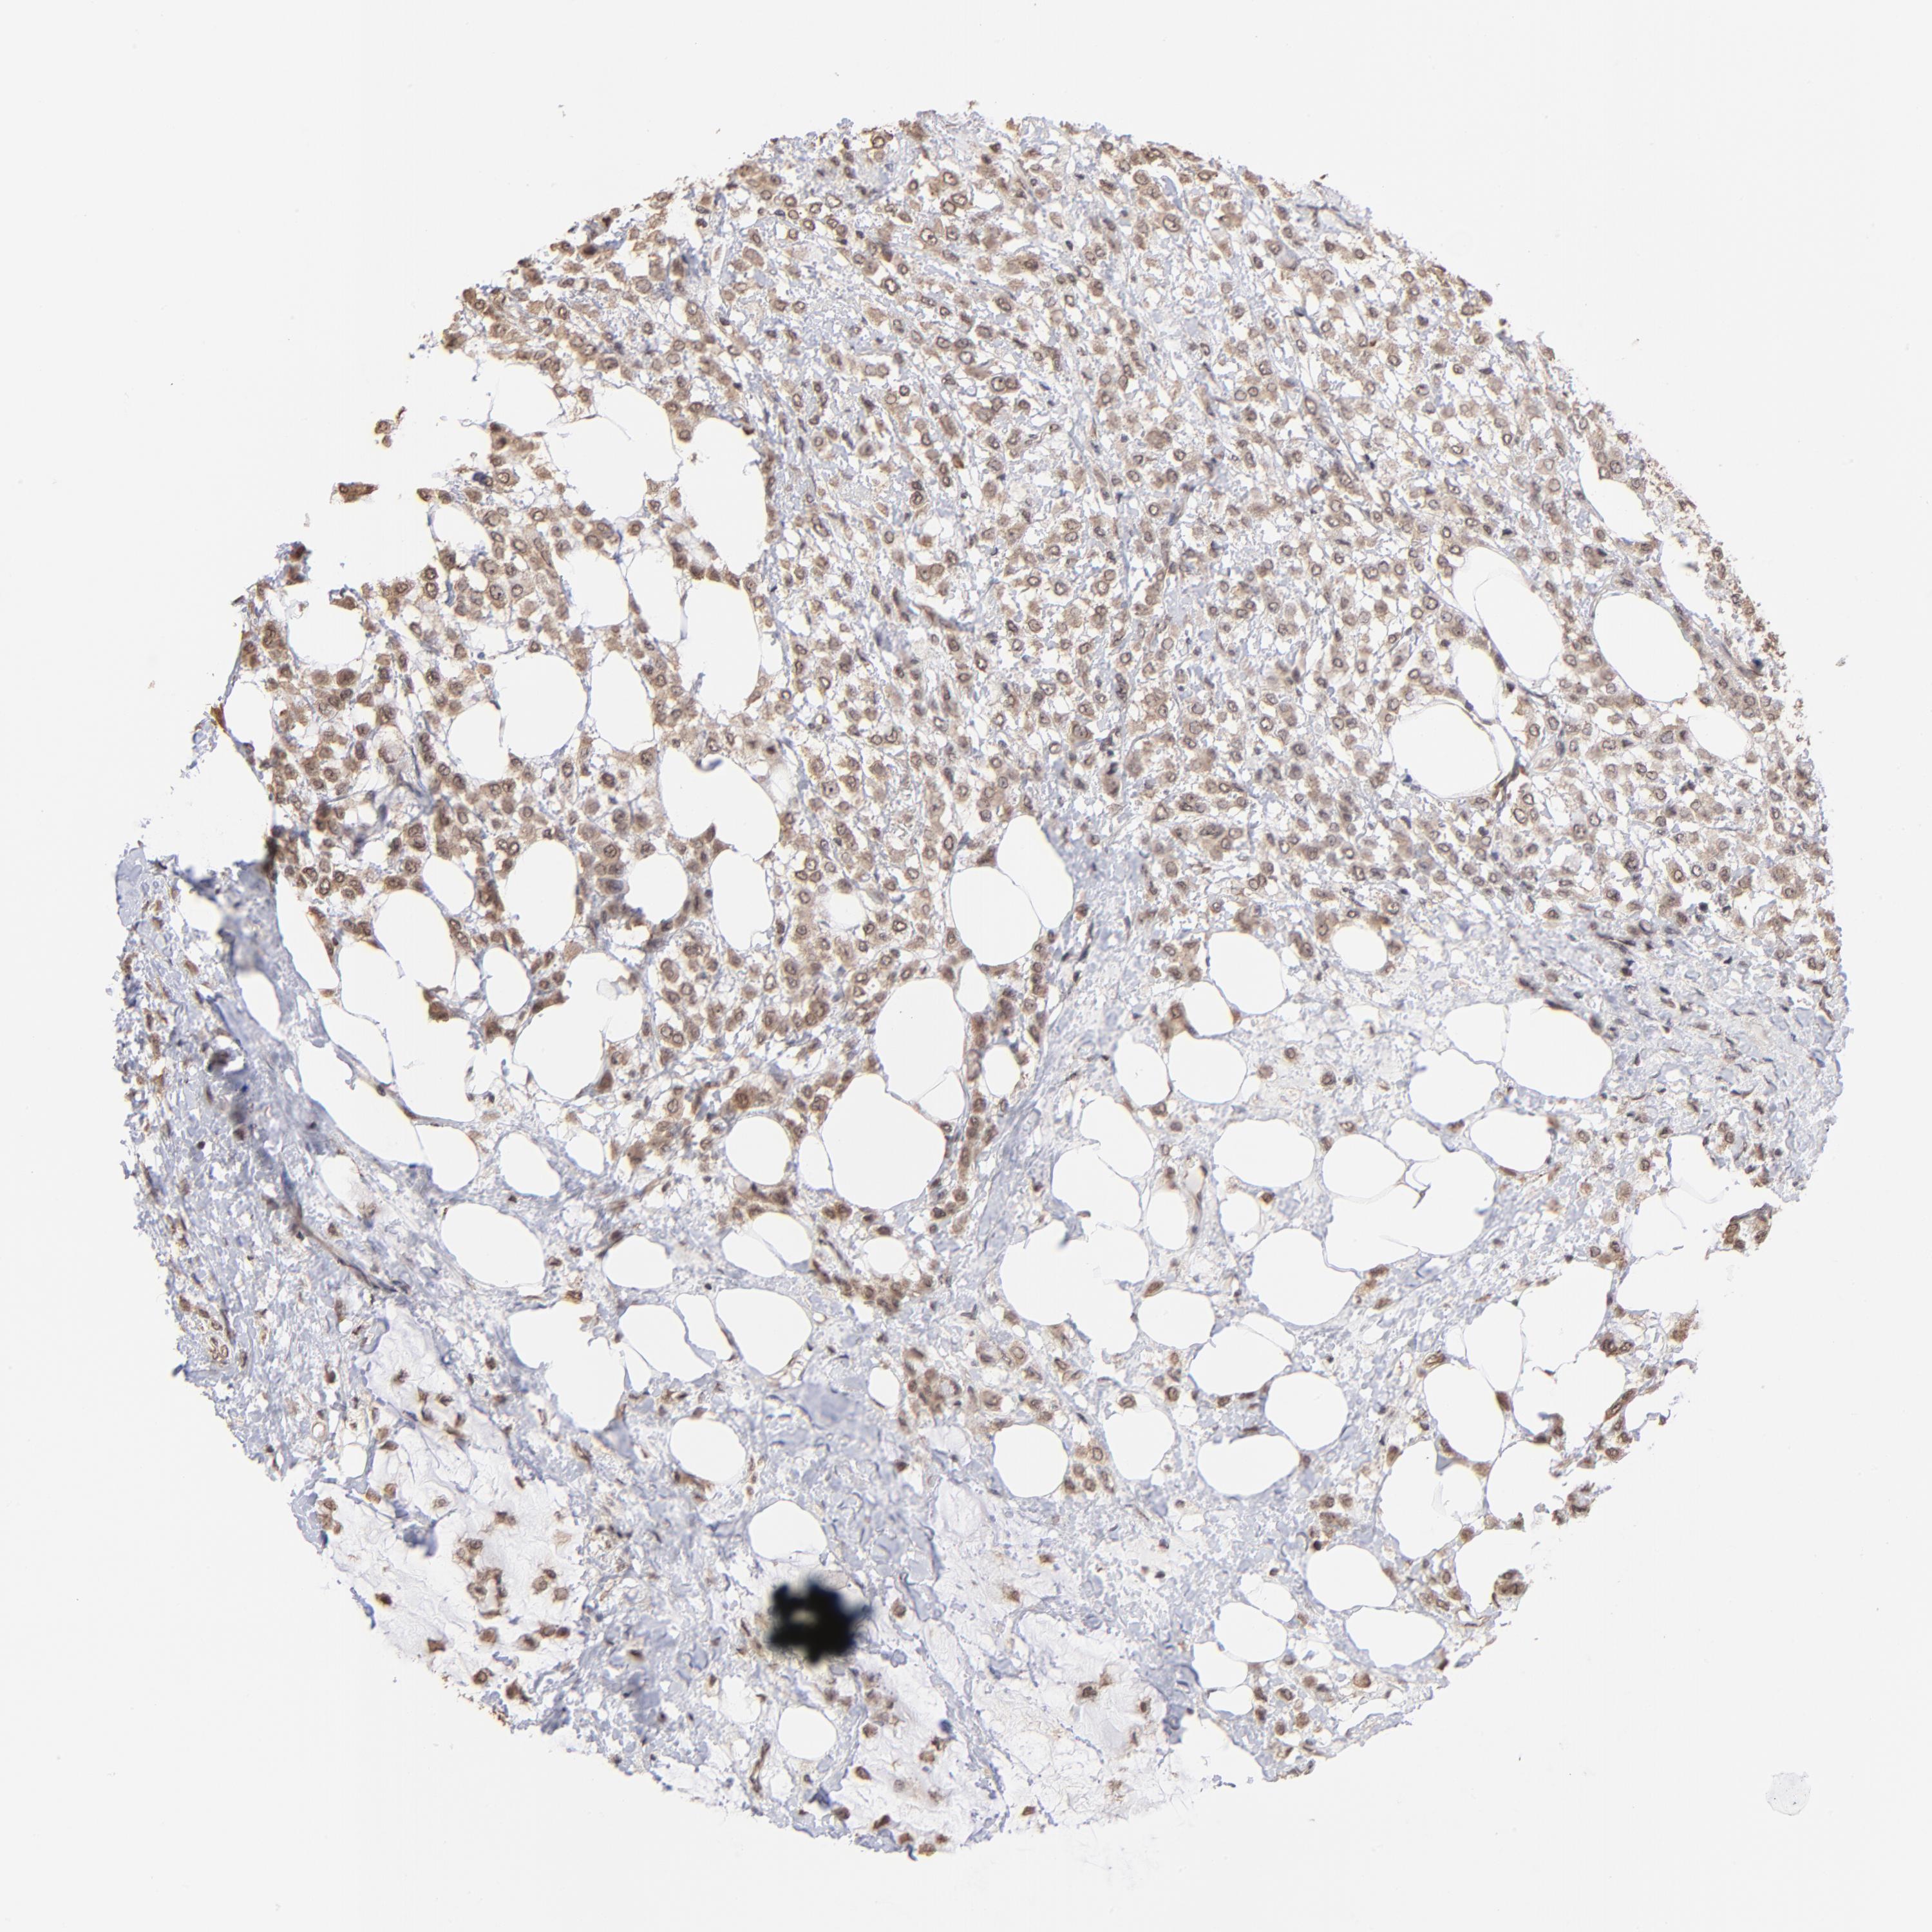

CANCER BREAST CANCER Show tissue menu

BRCA TCGA BRCA VALIDATION PROTEIN EXPRESSION

Breast cancer

Human cancer